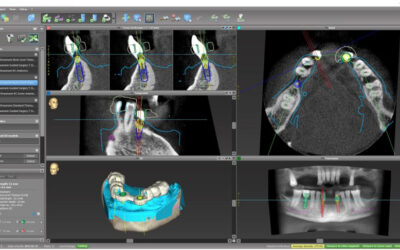

Utilizziamo l’innovativa tecnica dell’implantogia computer guidata: in che cosa consiste?

L’implantologia è quella disciplina della parodontologia che si occupa della sostituzione dei denti e delle loro radici mediante l’infissione nell’osso della mandibola e/o della mascella di viti in titanio, chiamate impianti.L’implantologia computer...